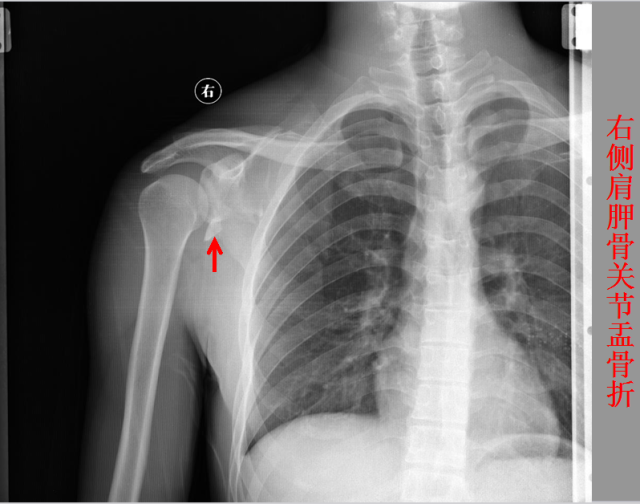

骨折篇

定义:骨折{Fracture}是指骨的完整性和连续性的折裂或粉碎。包括创伤性骨折、疲劳性骨折和病例理性骨折。 临床上以创伤性骨折*常见。